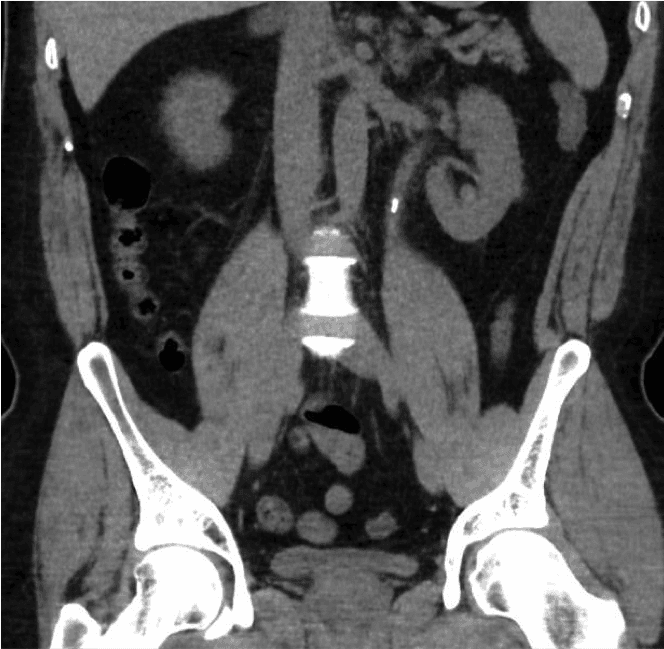

clinical burden on our healthcare system. Kidney stones may present incidentally on a scan performed for other reasons or present with symptoms such as pain, urine infection or hematuria (blood in the urine).